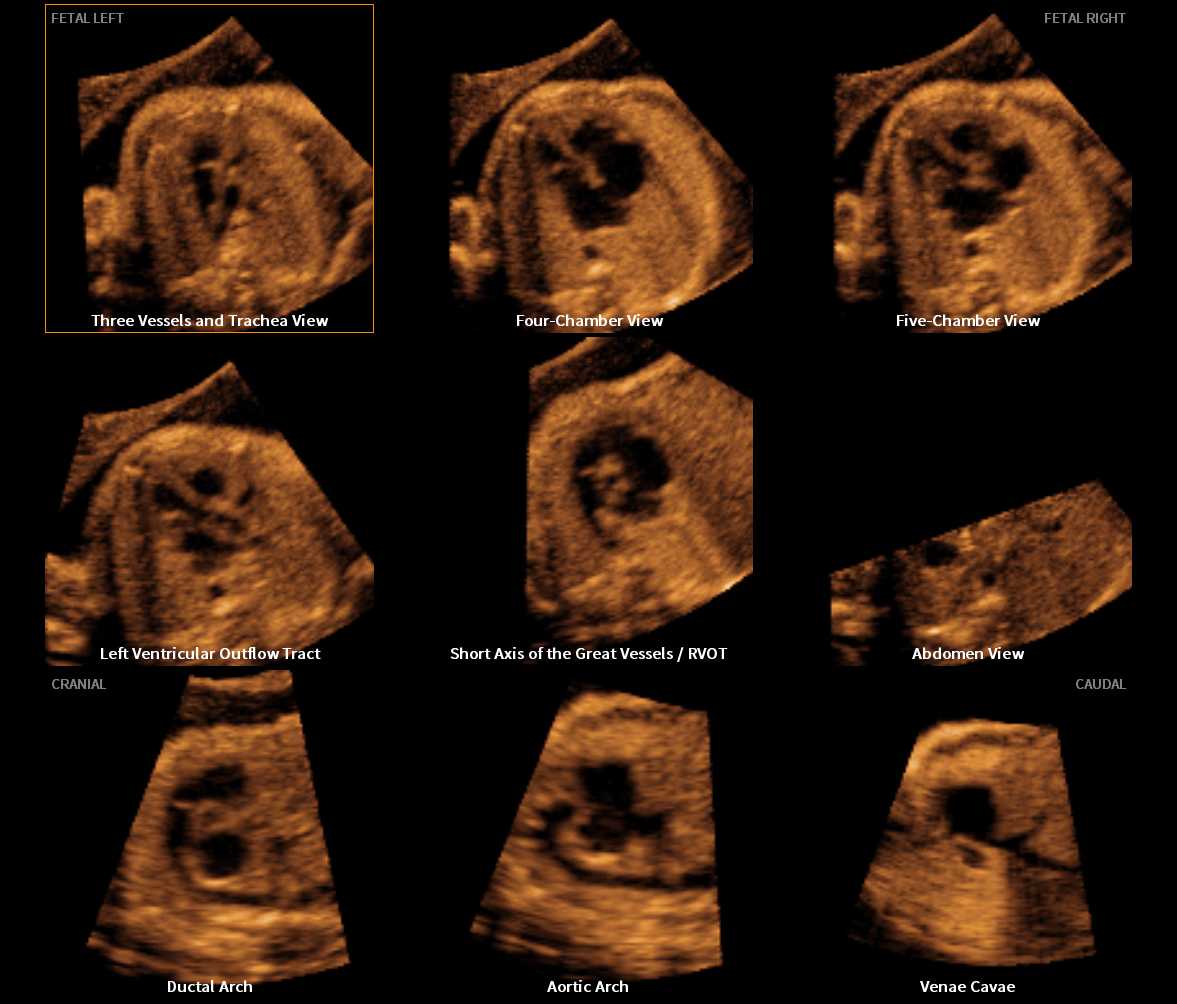

Professor Lami Yeo, M.D., from the Department of Obstetrics and Gynecology at the Wayne State University School of Medicine in Detroit, U.S., presented research on the diagnostic performance of Fetal Intelligent Navigation Echocardiography (5D Heart™) which showed a sensitivity of 98%, specificity of 93%, and accuracy of 95% for the prenatal detection of congenital heart disease*. She also explained that 5D Heart™ offers a rapid and simple solution to screen for and diagnose congenital heart disease by generating nine standard fetal echocardiography views in a single template display.

Additionally, novel research conducted on color Doppler Fetal Intelligent Navigation Echocardiography (5D Heart Color™) will be published in the October 2017 issue of the scientific journal Ultrasound in Obstetrics & Gynecology (UOG), which will also feature on its front cover, the prenatal diagnosis of congenital heart disease using 5D Heart color™.